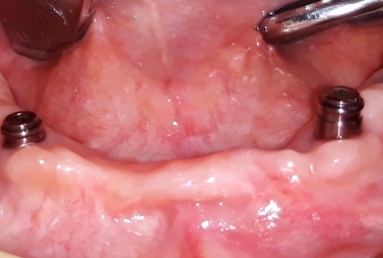

Mobile Prosthesis fixed with 4 locators on 4 Alpha BIO Nobel dental implants

Mobile Prosthesis fixed with 4 locators on 4 Alpha BIO Nobel dental implants.

The mobile prosthesis is fixed with 4 locators that firmly stabilise it. The mastication, talking and aesthetics is very comfortably and safely obtained.